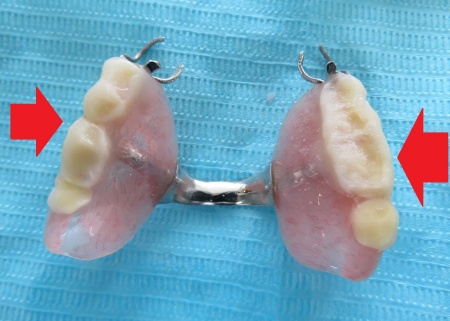

拝見したところ、上の奥歯には左右とも部分入れ歯が装着されていました。

詳しい検査を行った結果、下奥歯のセラミックの被せ物の影響で、噛み合っている上の入れ歯がすり減っていることが判明しました。

そのため、噛む面が薄くなり奥歯で十分に噛み合わず、前歯に負担が集中している状態です。

入れ歯の人工歯がすり減っています。